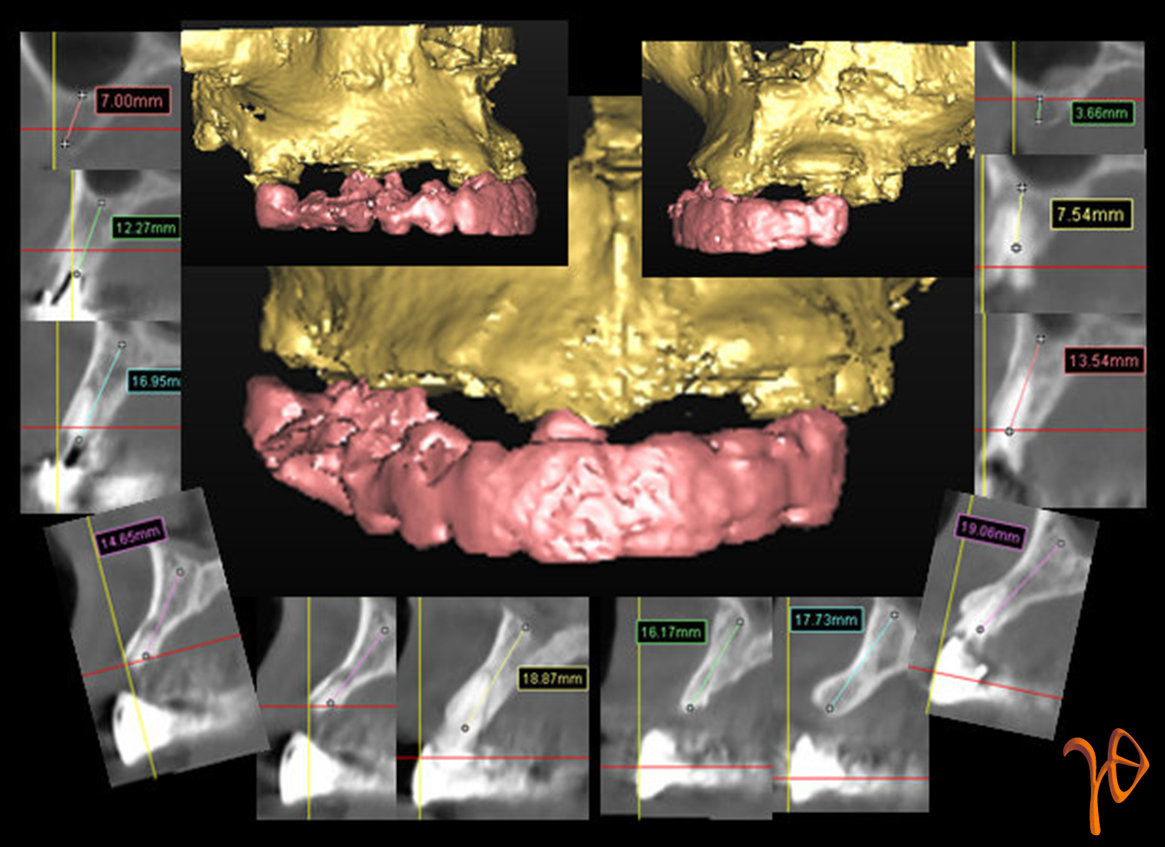

Η περίπτωσή μας αφορά ασθενή, που προσήλθε για ολική αποκατάσταση με εμφυτεύματα στην άνω και κάτω γνάθο. Από την μελέτη της άνω γνάθου, με την βοήθεια του λογισμικού Simplant(Εικόνα 2), προέκυψε σχέδιο για τοποθέτηση πέντε οδοντικών εμφυτευμάτων, εκ των οποίων το ένα με κλίση ώστε να αποφευχθεί η είσοδος στην κοιλότητα του ιγμορείου (θέση #25)(Εικόνα 3).

Εικόνα 2. Μελέτη όλων των cross-sections για το ύψος, το εύρος και την κλίση του οστού.

Εικόνα 3. Τρισδιάστατη ανασύνθεση(Simplant) των θέσεων επιλογής για την τοποθέτηση των εμφυτευμάτων. Σημειώστε την σχεδίαση του #25 σε σχέση με το ιγμόρειο(βέλος).